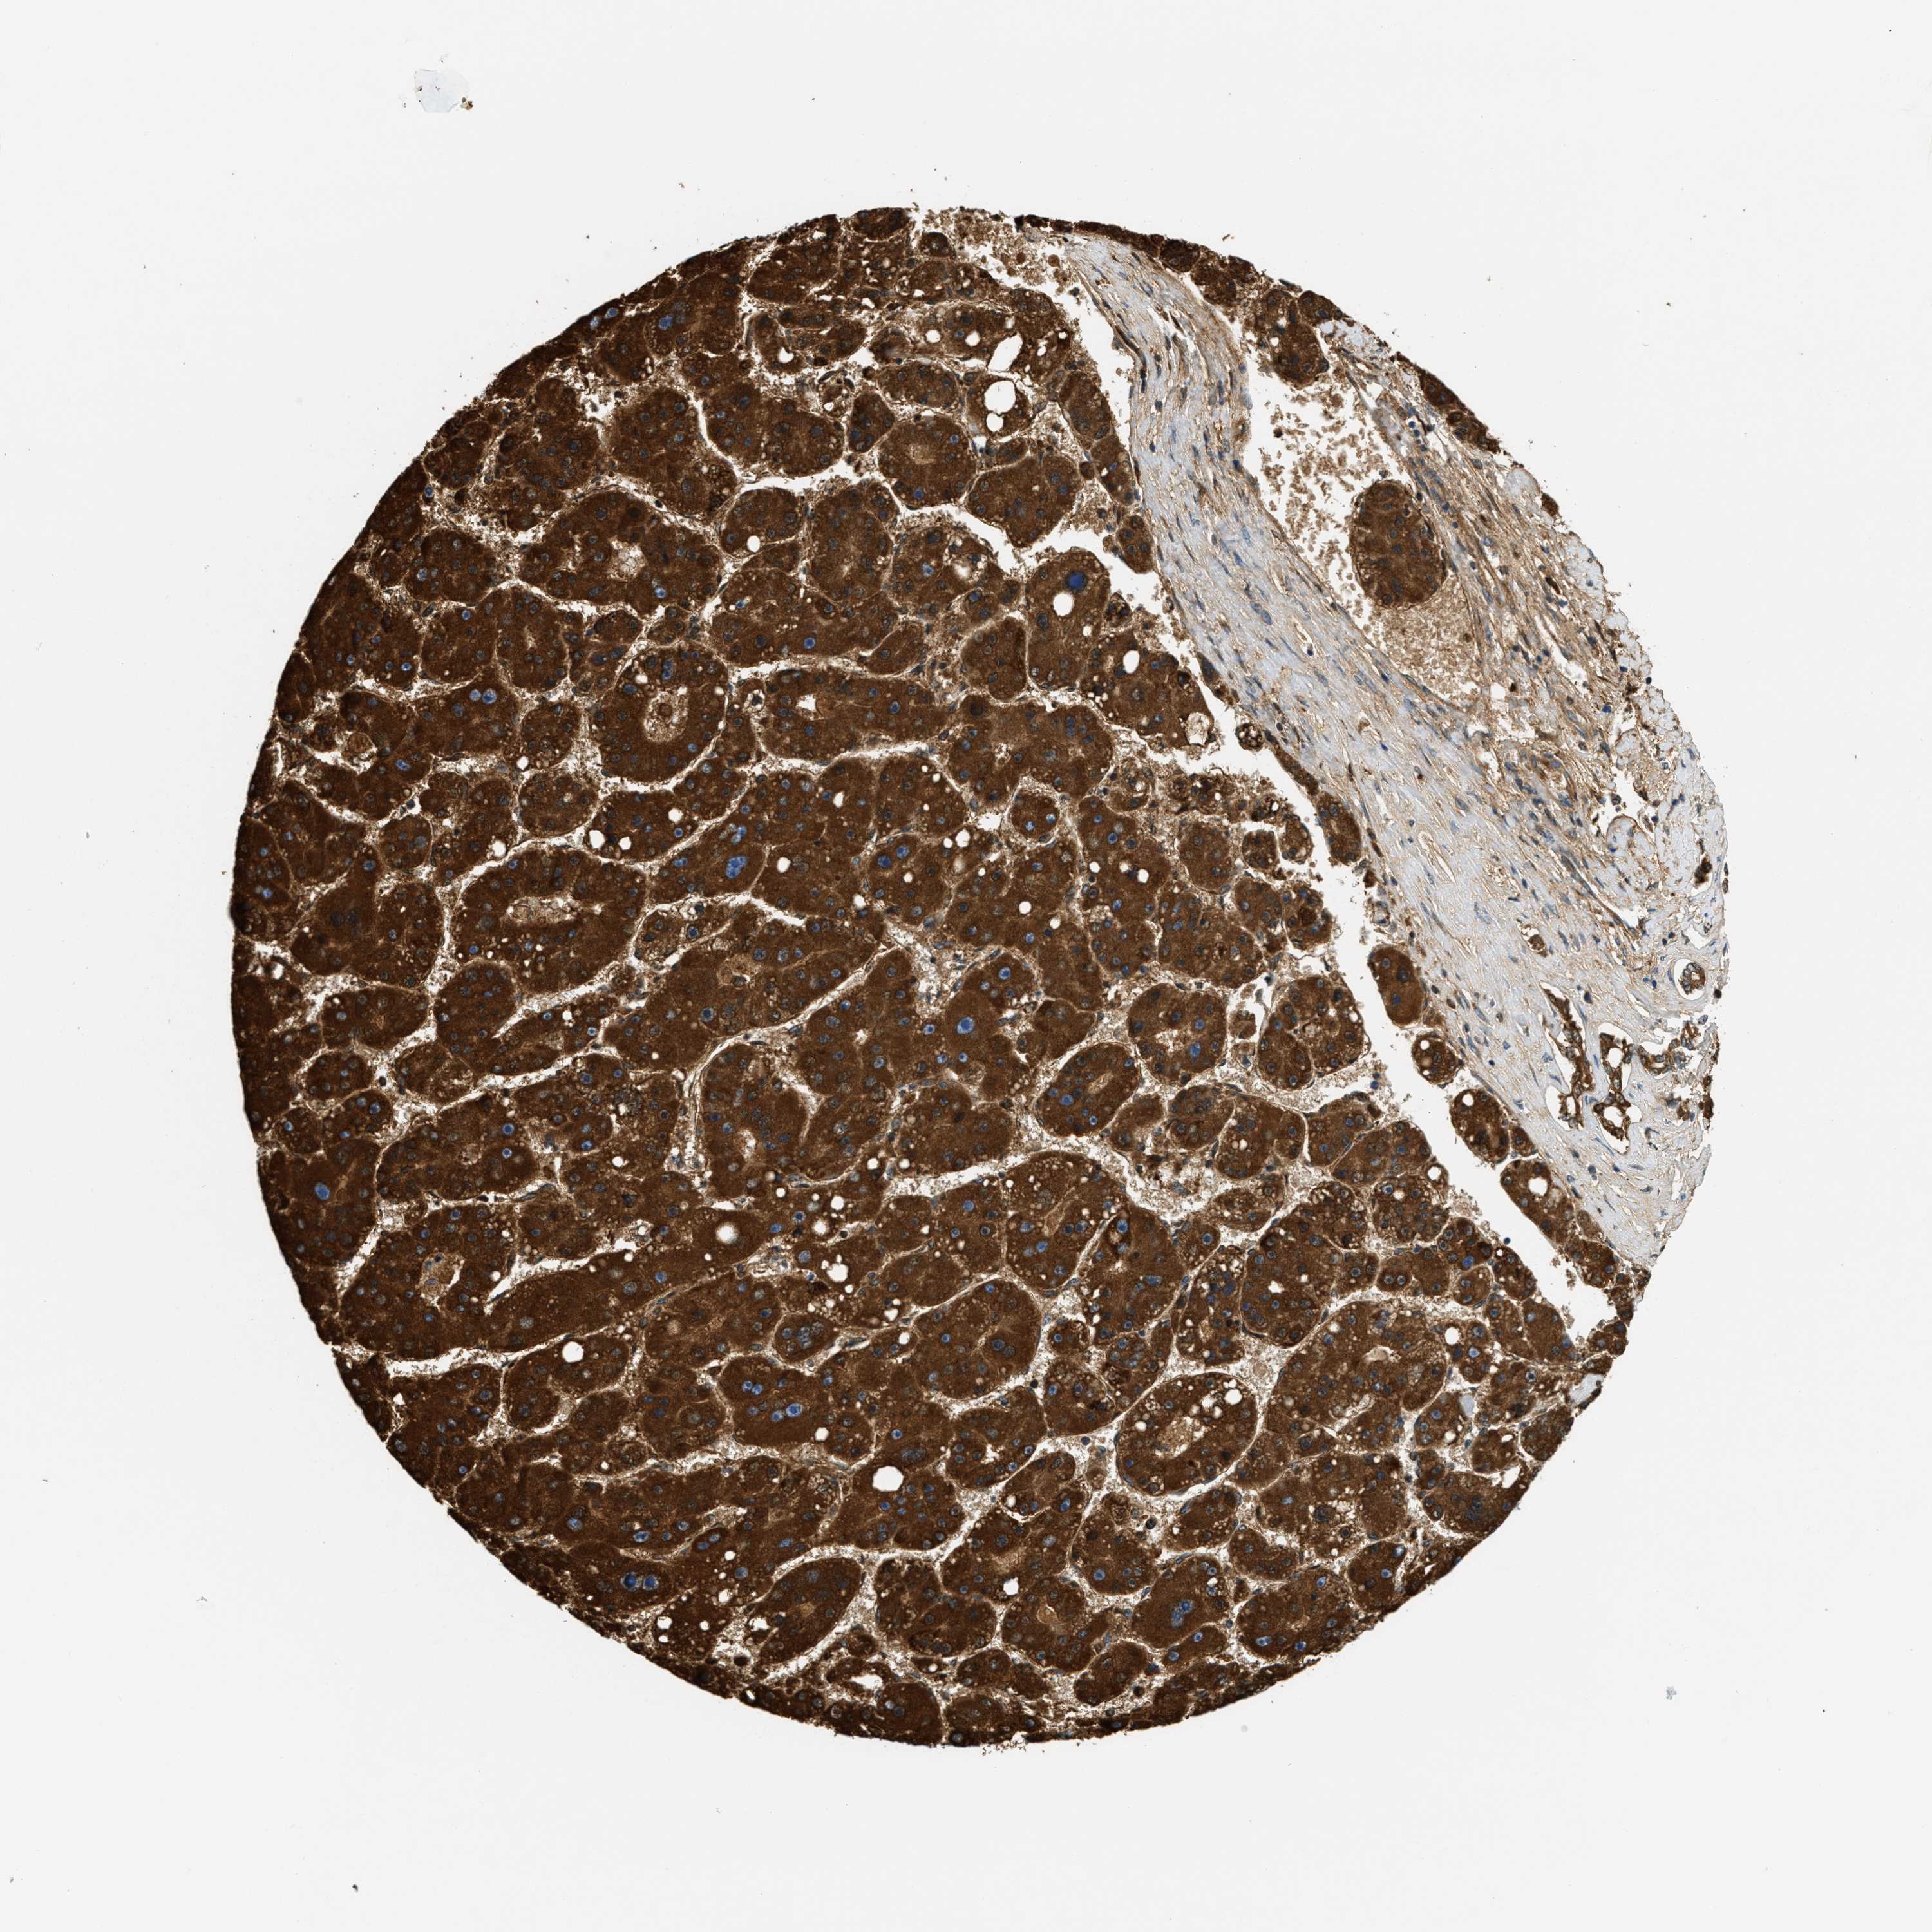

LIVER CANCER - Protein expressioni

A mouse-over function shows sample information and annotation data. Click on an image to view it in a full screen mode. Samples can be filtered based on level of antibody staining by selecting one or several of the following categories: high, medium, low and not detected. The assay and annotation is described here.

Antibody stainingi

Antibody staining in the annotated cell types in the current human tissue is reported as not detected, low, medium, or high, based on conventional immunohistochemistry profiling in selected tissues. This score is based on the combination of the staining intensity and fraction of stained cells.

Each image is clickable and will lead to virtual microscopy that enables deeper exploration of all samples and also displays staining intensity scores, fraction scores and subcellular localization as well as patient and tissue information for each sample.

Antibody HPA017379

Staining

High

Medium

Low

Not detected

Intensity

Strong

Moderate

Weak

Negative

Quantity

>75%

75%-25%

<25%

None

Location

Nuclear

Cytoplasmic/membranous

Cytoplasmic/membranous,nuclear

Carcinoma, Hepatocellular, NOS

Cholangiocarcinoma